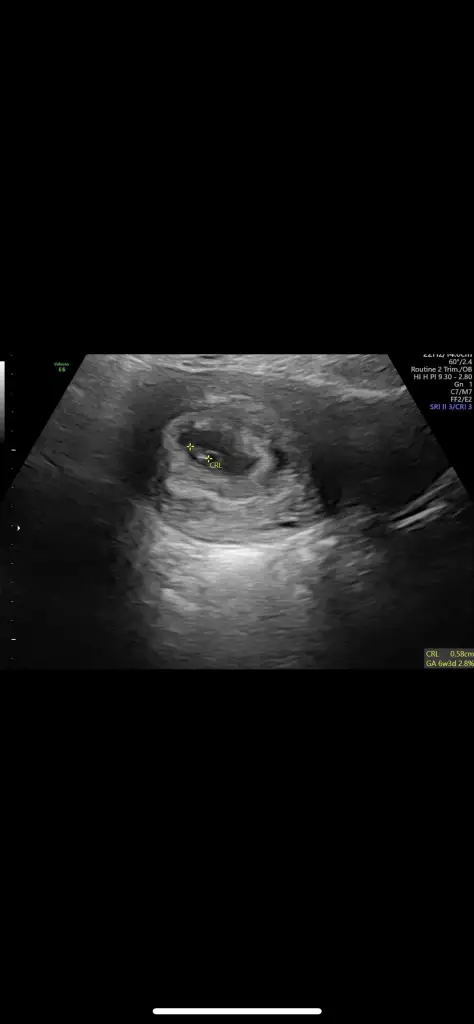

Merhaba benimkini de yorumlar mısın, 6, 7. Haftalara ait ultrason fotoğraflarımız karından çekildi

:)